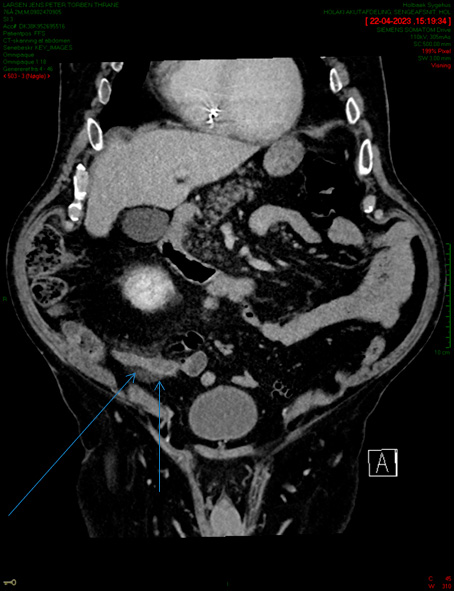

CT skanning af patient med appendicitis med 2 dages anamnese. Pile angiver fortykket appendix